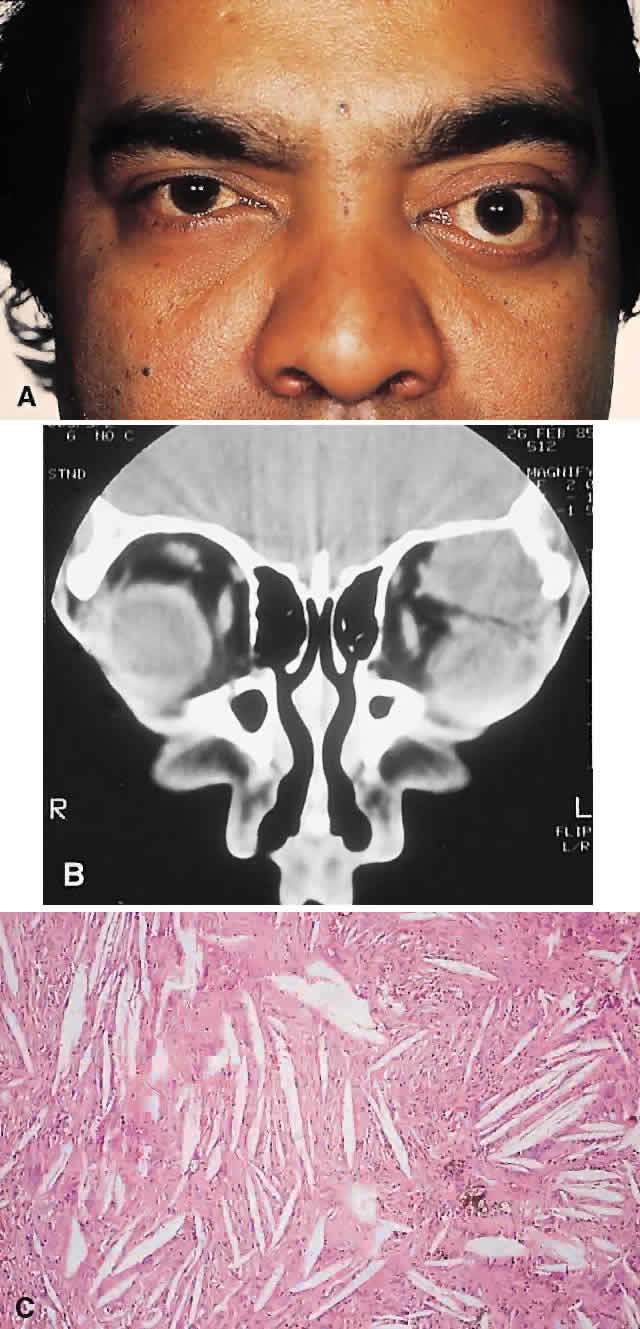

PRESENTATION. The site and the extent of disease are the major determinants of symptomatology. Facial asymmetry, proptosis, and globe displacement evolving over many years are the most common manifestations (Fig. 2). Nasolacrimal duct blockage, diplopia, nasal obstruction, malocclusion, raised intracranial pressure, and cranial nerve palsies also occur.25,28–30 Acute or subacute compressive optic neuropathy can arise as a result of intralesional hemorrhage, sphenoidal mucocele, or secondary aneurysmal bone cyst.31 A more chronic visual loss, although less commonly reported, may occur as a result of compression in the optic canal or at the chiasm. On occasion, a superimposed ischemic neuropathy in the context of chronic compression leads to an acute on chronic deterioration in vision.32

Fig. 2. A. A 20-year-old man presented with a longstanding history of left proptosis and facial asymmetry. B and C. Bone window CT scan showed extensive fibrous dysplasia involving the greater wing of the sphenoid in a sclerotic fashion and a more pagetoid appearance in the maxillary and ethmoidal regions. D and E. Dominant histologic features consisted of irregular trabeculae of woven bone in a fibrous stroma with minimal osteoblastic activity (E) surrounding the osteoid (hematoxylin-eosin; D × 20, E × 50).

IMAGING. In the craniofacial bones, fibrous dysplasia tends to expand the bone, with thinning of the overlying cortex. The margins are poorly defined, and the dysplasia transgresses suture lines; the proportion of mineralized to fibrous tissue determines the degree of radiolucency. Most cases demonstrate a relatively equal mixture, resulting in a pagetoid appearance. Where the fibrous element is predominant, there may be cystlike areas; a preponderance of mineralized tissue, however, results in a homogeneous, sclerotic, “ground-glass” picture. Fries34 reviewed 39 patients with fibrous dysplasia of the craniofacial bones and found a pagetoid pattern to be most common (56%), followed by sclerotic (23%) and cystlike (21%) appearances.

HISTOPATHOLOGY. Macroscopically, fibrous dysplasia consists of gritty, white-to-pink tissue, often with blood or serous-filled cystic areas. Histologically, there is a fibrous background containing trabeculae of woven bone. The stroma has variable amounts of collagen, fibroblasts, and vascularity. There may also be myxomatous areas and secondary aneurysmal bone cysts. The curvilinear bone trabeculae take on a variety of configurations, including C or Y shapes (so-called Chinese characters). These trabeculae sometimes have irregular margins as a result of the attachment of collagen fibers arising in the stroma. Cartilaginous nodules as well as small foci of lamellar bone are occasionally seen, but the vast majority of lesions contain immature woven bone. At its periphery, fibrous dysplasia permeates normal bone, and there may be areas of reactive bone with more prominent lamellar bone formation and osteoblastic rimming. Sequential biopsies of fibrous dysplasia from childhood to adult life have shown that the histologic picture does not change with time.36